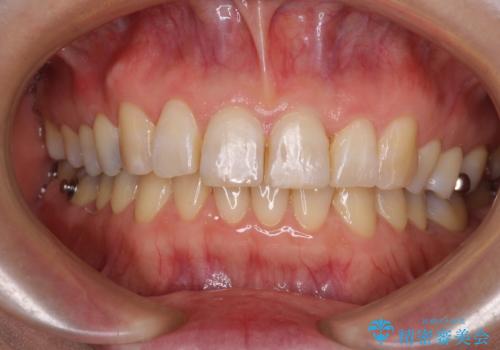

- 治療期間

- 7年5ヶ月

- 治療回数

- 10-30回